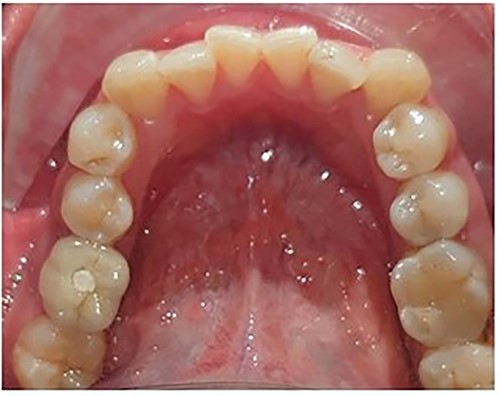

Following the placement of miniscrews, immediate loading was done with 100 g of intrusive force using a short power chain. The power chain was passed and engaged onto the composite button to ensure the forces are directed occlusally and there is no slippage. The patient was followed up at 4-week intervals and the power chain was replaced with one link, which was reduced at each appointment. After the first month, the dental implant was placed to replace the mandibular first molar. After 5 months of intrusion, the desired occlusal clearance was achieved and the upper and lower impressions were recorded (Fig. 2). For retention in the upper arch, the patient was given a clear vacuum retainer, while the crown was placed on the implant to prevent any relapse and to achieve good occlusion.

The intrusion process with placement of the prosthetic crown at the completion stage.

Allowed for placement of full coverage crown on the implant placed to replace the mandibular first molar (Fig. 4).

Full coverage crown placed on the implant to replace the mandibular first molar.